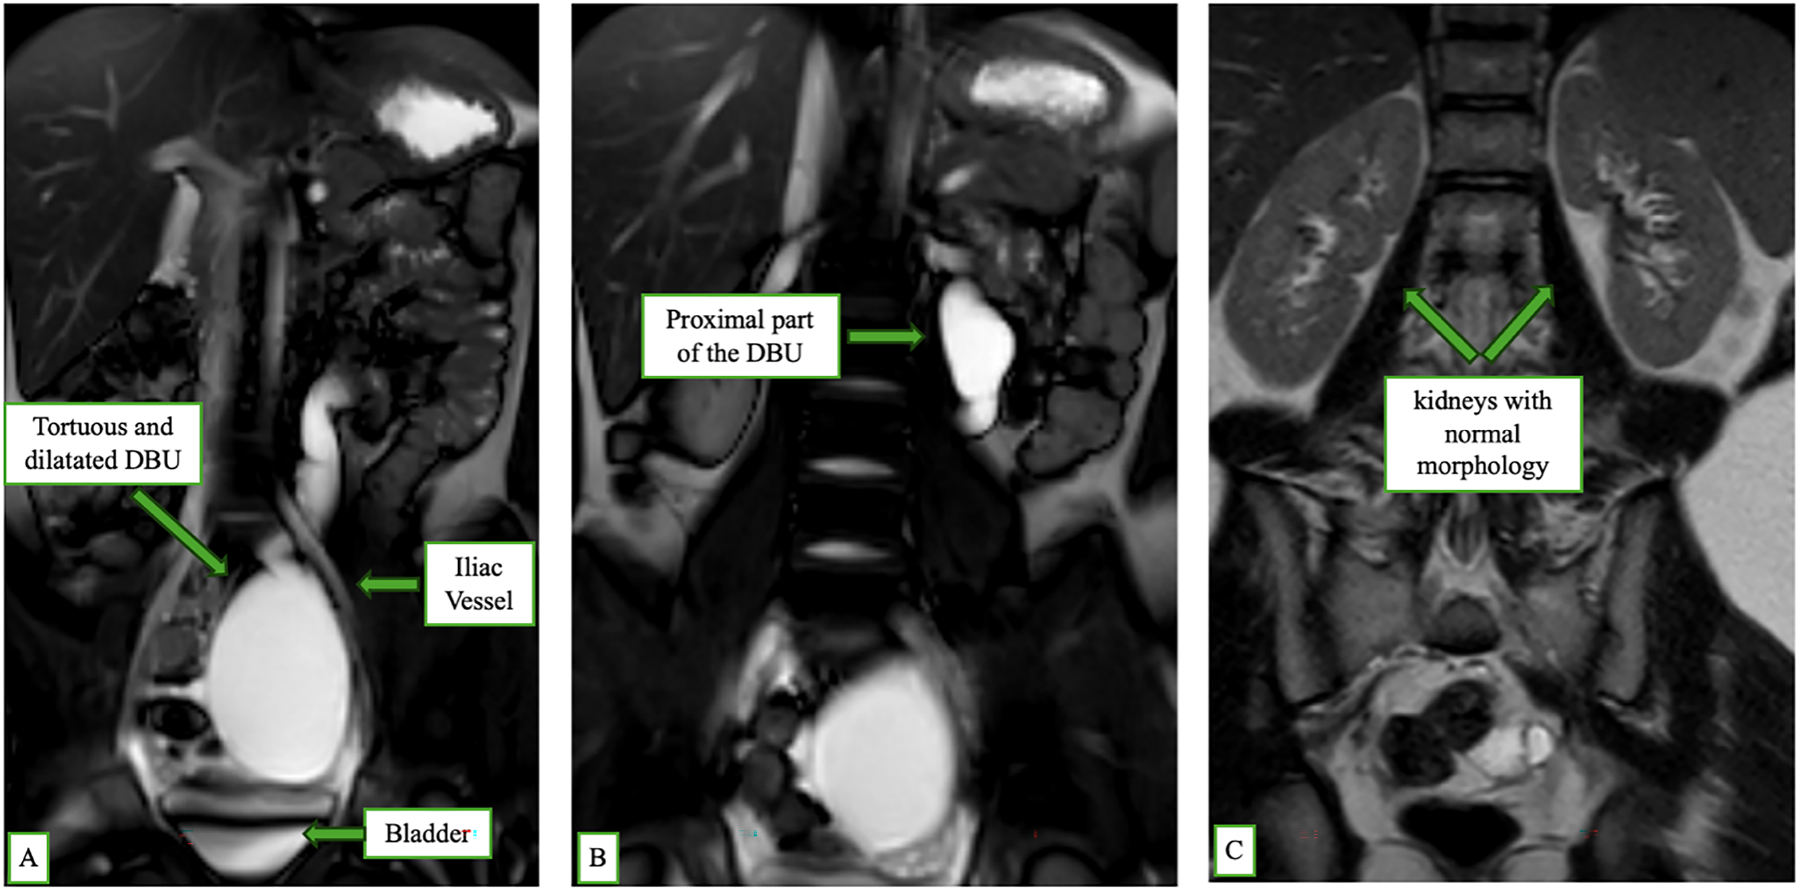

She came to our attention, at IRCCS Meyer Children’s Hospital, Florence, Italy, with an incidental ultrasound (US) picture of left hydroureteronephrosis. The US showed a renal pelvis (measuring 2 cm) with a tortuous ureter, together with a para-bladder cystic formation of uncertain nature measuring 5–6 cm. Physical examination was not significant. To further evaluate these findings, we performed an abdominal magnetic resonance imaging (MRI), which reported: “A large, fluid-filled tubular structure is present in the left retroperitoneal region, running alongside the left ureter. It extends about 30 cm from the compressed left renal pelvis to the pelvic cavity, following a tortuous path with variable caliber. A saccular dilation (7 × 6 cm) is seen at the lumbosacral transition before it narrows and extends toward the left ovary. There is no clear connection to the renal calyces or bladder, and it remains non-opacified in urographic imaging, indicating it is a non-functioning, dilated ureteral remnant likely from a regressed renal unit.” (Figure 1).

FIGURE 1. Magnetic resonance imaging (MRI) coronal scan showing features of double blind-ending ureter (DBU): (A) A tortuous and dilated DBU running parallel to the normal left ureter, located anterior to the iliac vessel and bladder. (B) Proximal portion of the DBU without connection to the renal pelvis. (C) Bilateral kidneys with normal morphology and no evidence of hydronephrosis